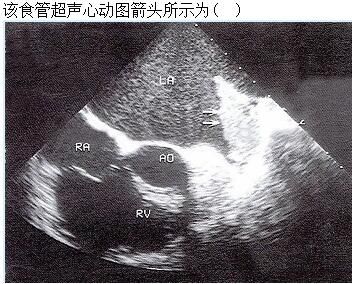

A.左心耳血栓

B.左房黏液瘤

C.左房梳状肌

D.以上都不是

E.左房赘生物